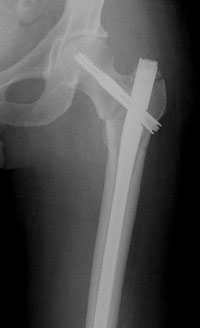

The intramedullary nail is placed directly into the marrow canal of the bone through an opening made at the top of the greater trochanter. A lag screw is then placed through the nail and up into the neck and head of the hip. As with the compression hip screw, sliding of the lag screw and impaction of the fracture take place.

At the subtrochanteric level, most fractures are managed with a long intramedullary nail together with a large lag screw or they are managed with screws that capture the neck and head of the femur or the area immediately underneath it, if it has remained intact.

In order to keep the bones from rotating around the nail or from shortening ("telescoping") on the nail, additional screws may be placed at the lower end of the nail in the area of the knee. These are called interlocking screws.

Repair of an intertrochanteric fracture with an intramedullary nail. The nail is in the hollow cavity of the femur (thighbone) rather than on the side of it (as with a plate).

Repair of subtrochanteric fracture with a long intramedullary nail.

Interlocking screws at the end of the nail make the fixation more secure.